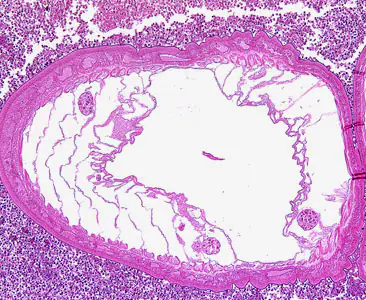

Acanthocephalans in tissue, stained with hematoxylin and eosin (H&E).